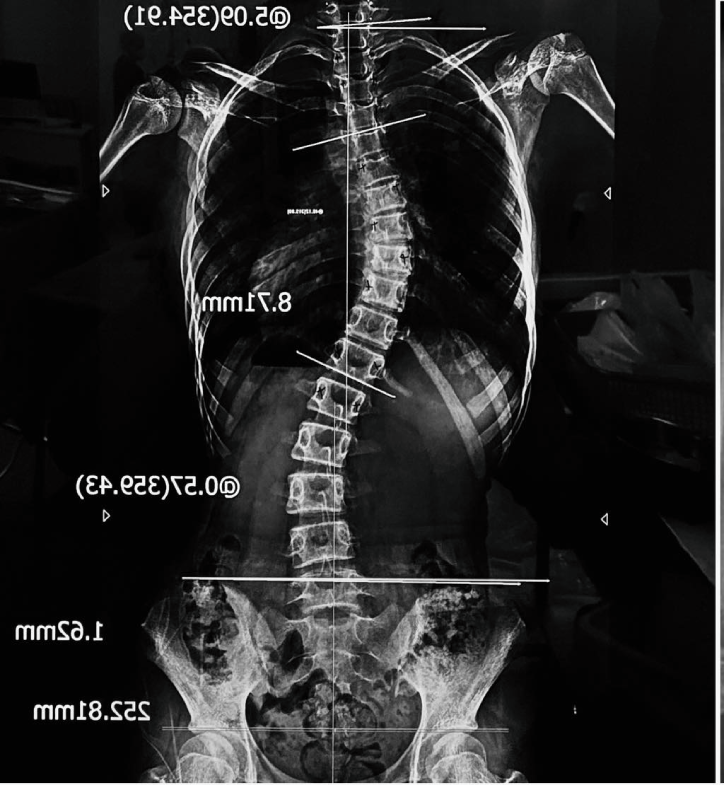

Bác sĩ Trần Trung Kiên - chuyên khoa Chấn thương chỉnh hình, Bệnh viện Đại học Y Hà Nội cho biết, vẹo cột sống là bệnh lý rất dễ chẩn đoán, chỉ cần chụp X-quang là có thể xác định. Tuy nhiên, chính vì dễ nhận biết nên thời gian qua xuất hiện nhiều dịch vụ, phòng tập, “chuyên gia” đưa ra các liệu trình điều trị thiếu cơ sở khoa học.

Tùy mức độ, bác sĩ sẽ chỉ định theo dõi, tập phục hồi chức năng, đeo nẹp hoặc phẫu thuật. Trong đó, các trường hợp nhẹ có thể theo dõi định kỳ, còn trường hợp nặng (trên 40-50 độ) có thể cần can thiệp phẫu thuật.